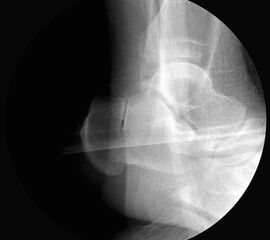

Bei Rückfussfehlstellungen ist meist eine knöcherne Korrektur des Kalkaneus indiziert. Dabei wird das Fersenbein im Bereich des Tuber calcanei durchtrennt und der Achillessehnenansatz nach medial oder lateral geschoben. Zusätzlich ist eine Rotation des Tuber möglich, wodurch sich der Korrektureffekt noch verstärkt. Durch die Wahl der Osteotomieebene kann die Verscheibung mit einer Verlängerung oder Verkürzung des Fersenbeins kombiniert werden. Die Osteosynthese erfolgt typischerweise durch perkutan eingebrachte Schrauben.

Röntgenaufnahmen des Fußes d.p., streng seitlich und schräg unter Belastung. Saltzmann Aufnahme zur Beurteilung der Rückfussachse.

Operationsplanung anhand der Röntgenaufnahmen unter Beachtung wichtiger radiologischer Landmarks wie Rückfussachse, Metatarsale I – Talushals-Achse im dp und lateralen Strahlengang (Abbildung 1 und 2).

Kanülierte Schrauben bis 80 mm Länge.

Kirschnerdraht mit 2,0 mm zur Verschiebung des Tuber calcanei.